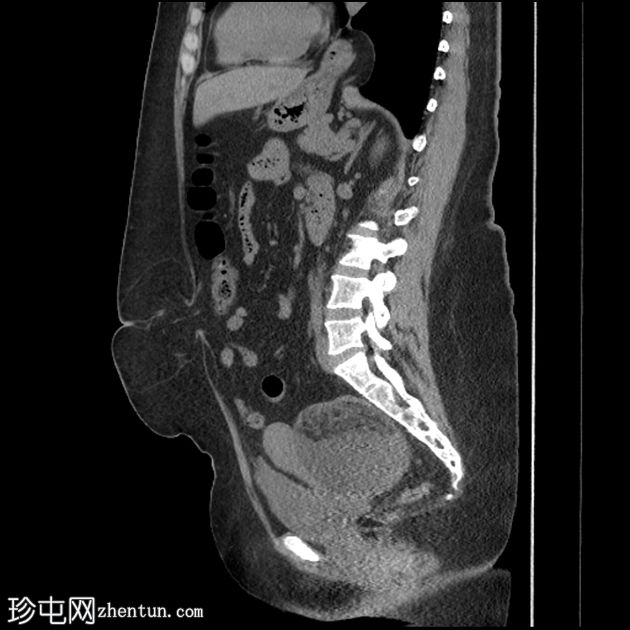

CT

轴位

平扫

可见一主要为囊性肿块,大小为10.1 x 7.3 x 8厘米,囊内含有脂肪球。囊壁可见钙化,并对直肠乙状结肠造成压迫。